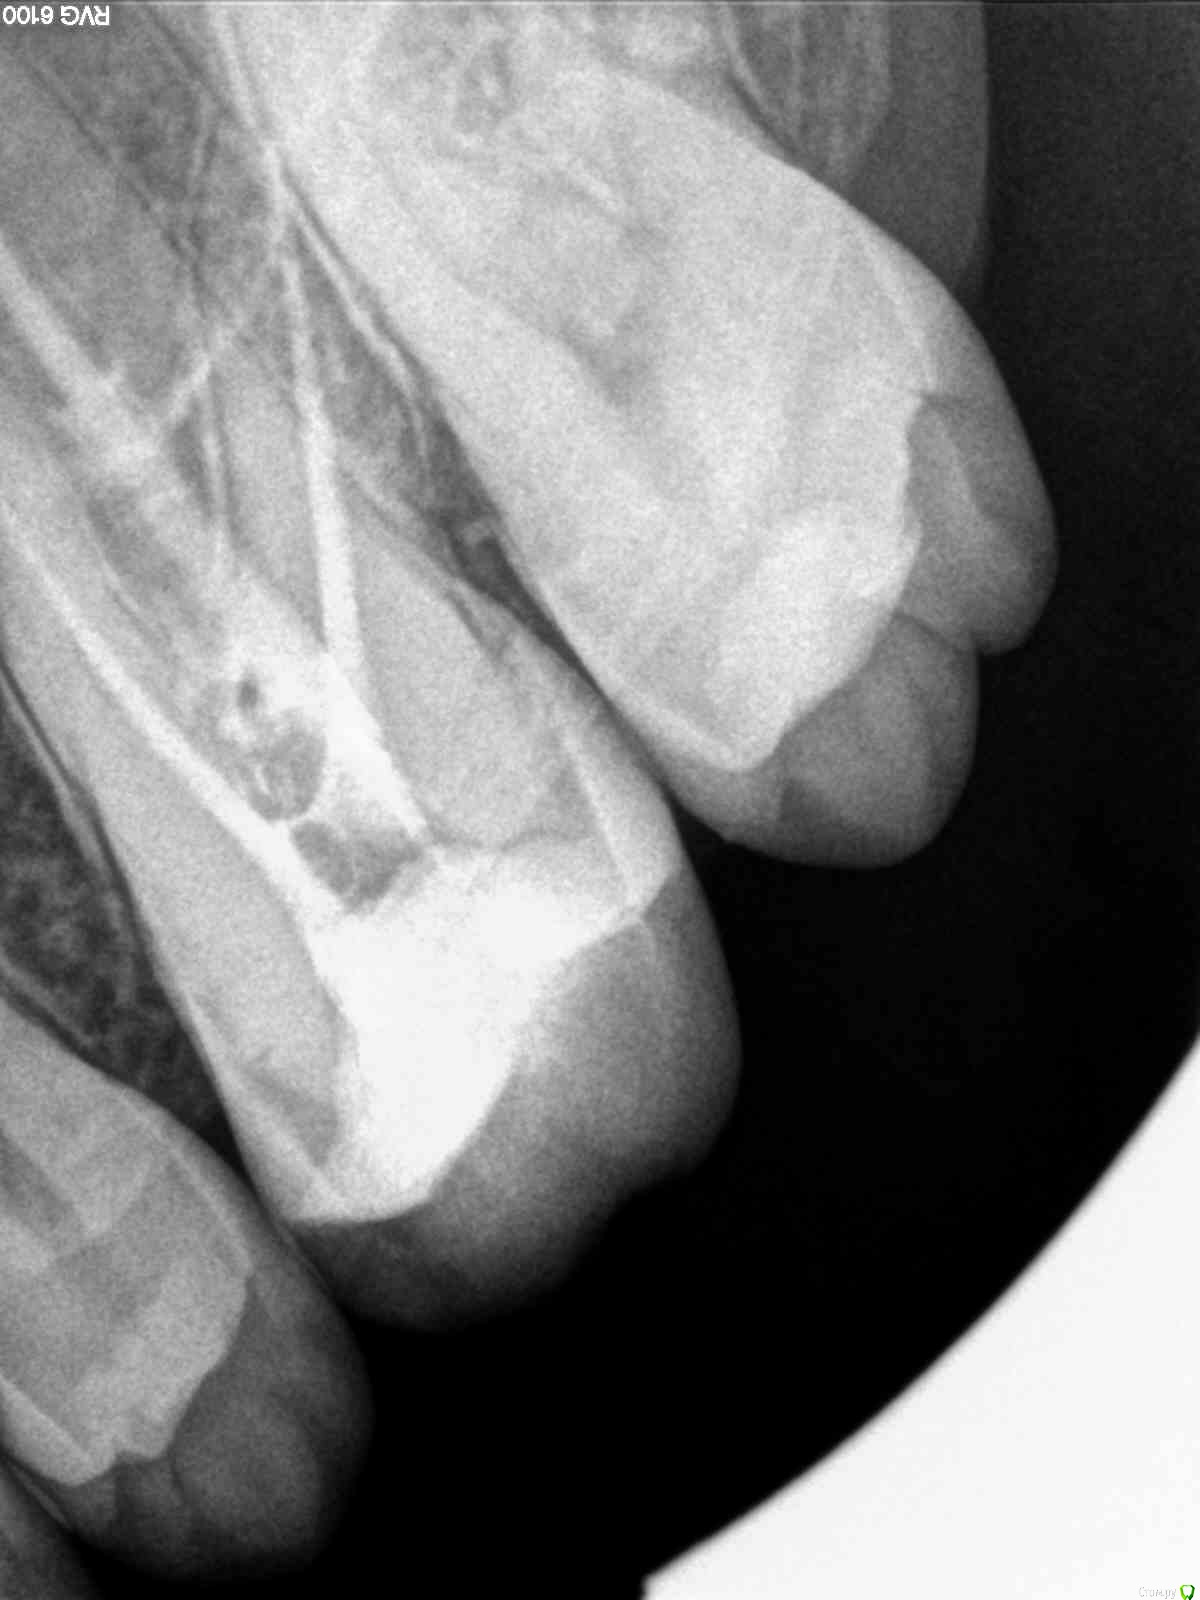

SolnceSamara Опубликовано 24 октября, 2015 Поделиться Опубликовано 24 октября, 2015 почернела старая пломба в давно пролеченной шестерке (сверху). Врач заменила пломбу но зуб болел при надавливании, заменили пломбу повторно-все равно осталась боль, сменила врача-снова сменили пломбу-снова болит, решили депульпировать-снова вынули пломбу, поставили временную-неделю проходила с временной-через неделю окончательно депульпировали, поставили постоянную. Сначало поболело 3 дня, и вроде прошло, хотя остался дискомфорт при надавливании. Прошло 3 недели, боль усилилась, теперь болит не только при надавливании иногда просто звеняще-ноющее ощущение нарастает. Пью нимесил. Посоветуйте что делать-что не так? Снимки прилагаю-делали на протяжении всйх операций (до и после).Разьяснение по снимкам :R1-29/08/15R2,R3-25/09/15R4-R7-28/09/15 Ссылка на комментарий

red_butler Опубликовано 24 октября, 2015 Поделиться Опубликовано 24 октября, 2015 Коллеги поправят, но выглядит как пломбирование одиночным штифтом. Возможно пропущен четвертый канал. Нужна ревизия корневых каналов. 2 Ссылка на комментарий

DmitrySH Опубликовано 24 октября, 2015 Поделиться Опубликовано 24 октября, 2015 Коллеги поправят, но выглядит как пломбирование одиночным штифтом. Возможно пропущен четвертый канал. Нужна ревизия корневых каналов. Все верно. Ссылка на комментарий

SolnceSamara Опубликовано 24 октября, 2015 Автор Поделиться Опубликовано 24 октября, 2015 (изменено) да К своему врачу обращались?Она предпредила что если вернется боль-нужно 3д снимок зуба делать. Я и решила перед снимком проконсультироваться на форуме, т.к. уже не знаю в чем причина-в зубе, во враче? Мало ли врачебная ошибка, а врач не признается просто. Я то не специалист- в снимках не разбираюсь... А по данным снимкам 4ый канал не видно? Боюсь потерять зуб... 5ый раз рассверливать...если не 6й будут((( Изменено 24 октября, 2015 пользователем SolnceSamara Ссылка на комментарий

red_butler Опубликовано 24 октября, 2015 Поделиться Опубликовано 24 октября, 2015 Кт неплохо бы сделать, но все равно нужно лечит. Ссылка на комментарий